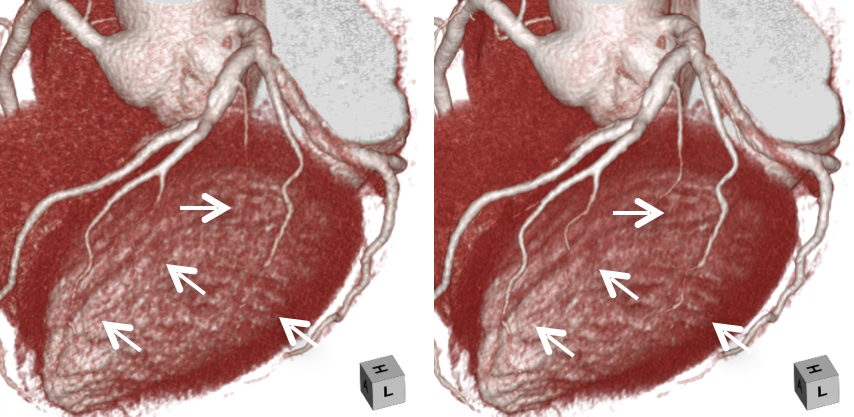

キヤノンメディカルシステムズが開発したPrecise IQ Engine(PIQE)によるディープラーニングの画像によって、冠動脈CT検査で評価が難しい石灰化やステントに接する部分の描出が向上されるため、さらに正確な画像診断が可能となりました。

石灰化症例:左の従来画像と比較して、右の高精細ディープラーニング画像では血管周囲の白い石灰化部分がシャープに描出されています。

左の従来画像と比較して、右の高精細ディープラーニング画像では矢印の細い血管も明瞭に描出されています。